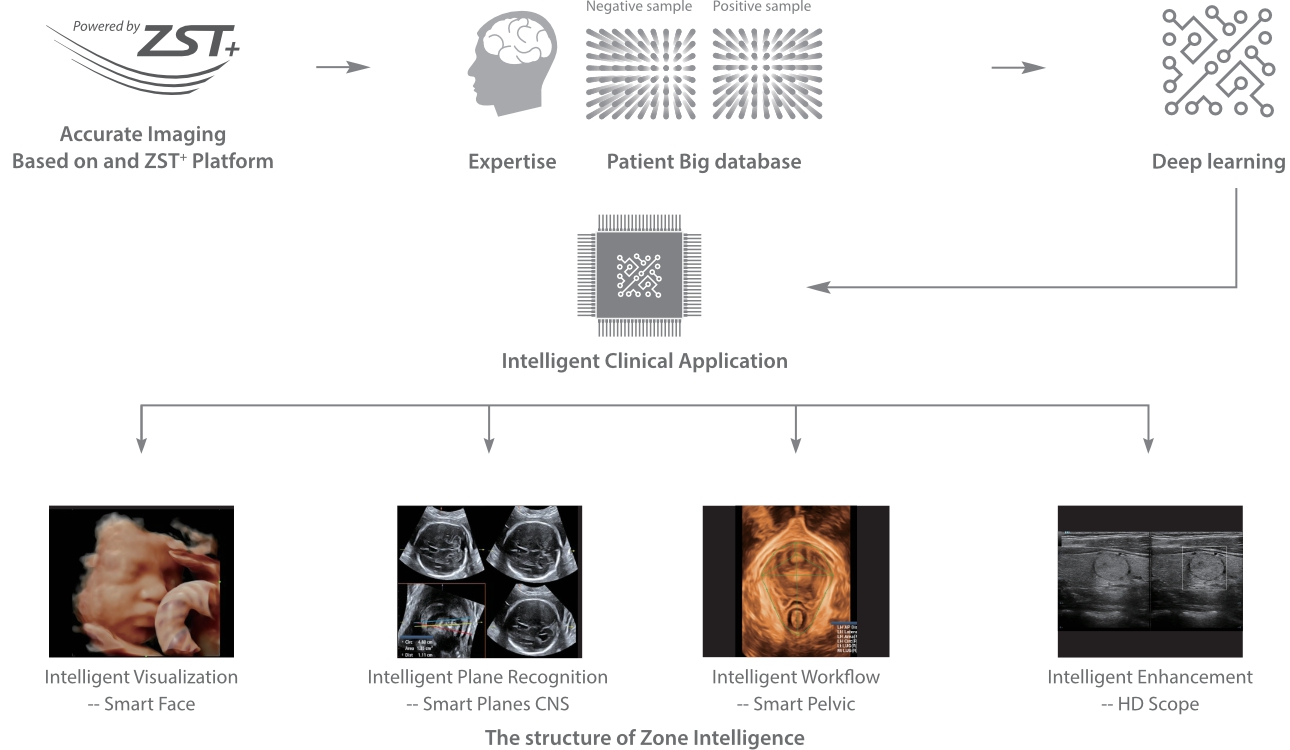

Sejak didirikan, Mindray terus mencari cara baru untuk meningkatkan keandalan diagnostik. Didukung Teknologi ZONE Sonography? terkini, platform ZST+ baru Resona 7 meningkatkan kualitas gambar ultrasound melalui pengambilan zona dan pemrosesan data saluran.

Selain kualitas gambar premium, Resona 7 juga meningkatkan kemampuan penelitian klinis dengan V Flow revolusioner untuk evaluasi hemodinamika vaskular, serta pengambilan penampang tercanggih dari rangkaian data 3D untuk diagnosis CNS pada janin. Kombinasi pengoperasian multisentuh berbasis gerakan yang paling intuitif dengan semua fitur klinis penting membuat Resona 7 menjadi gebrakan baru dalam inovasi ultrasound.